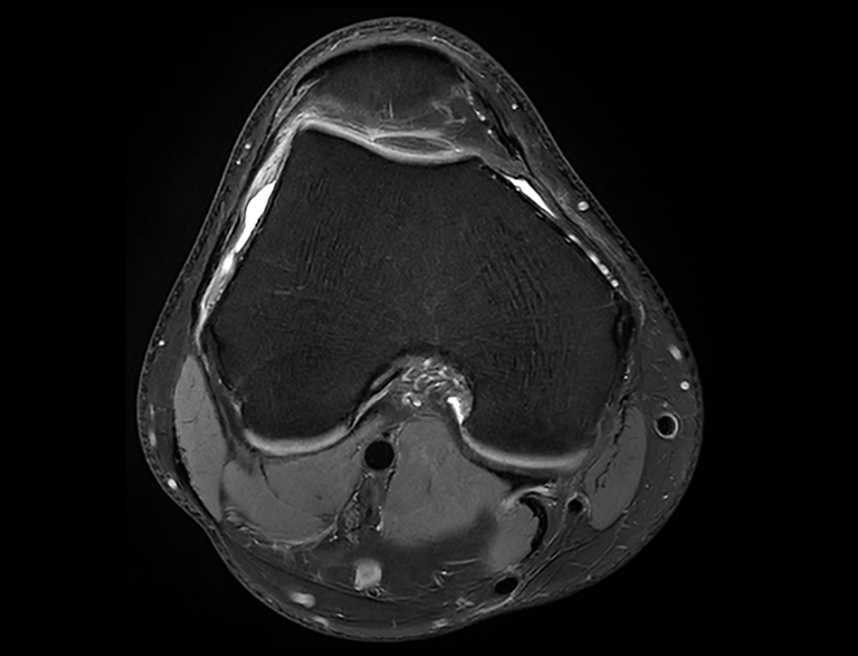

膝关节 PDW FS